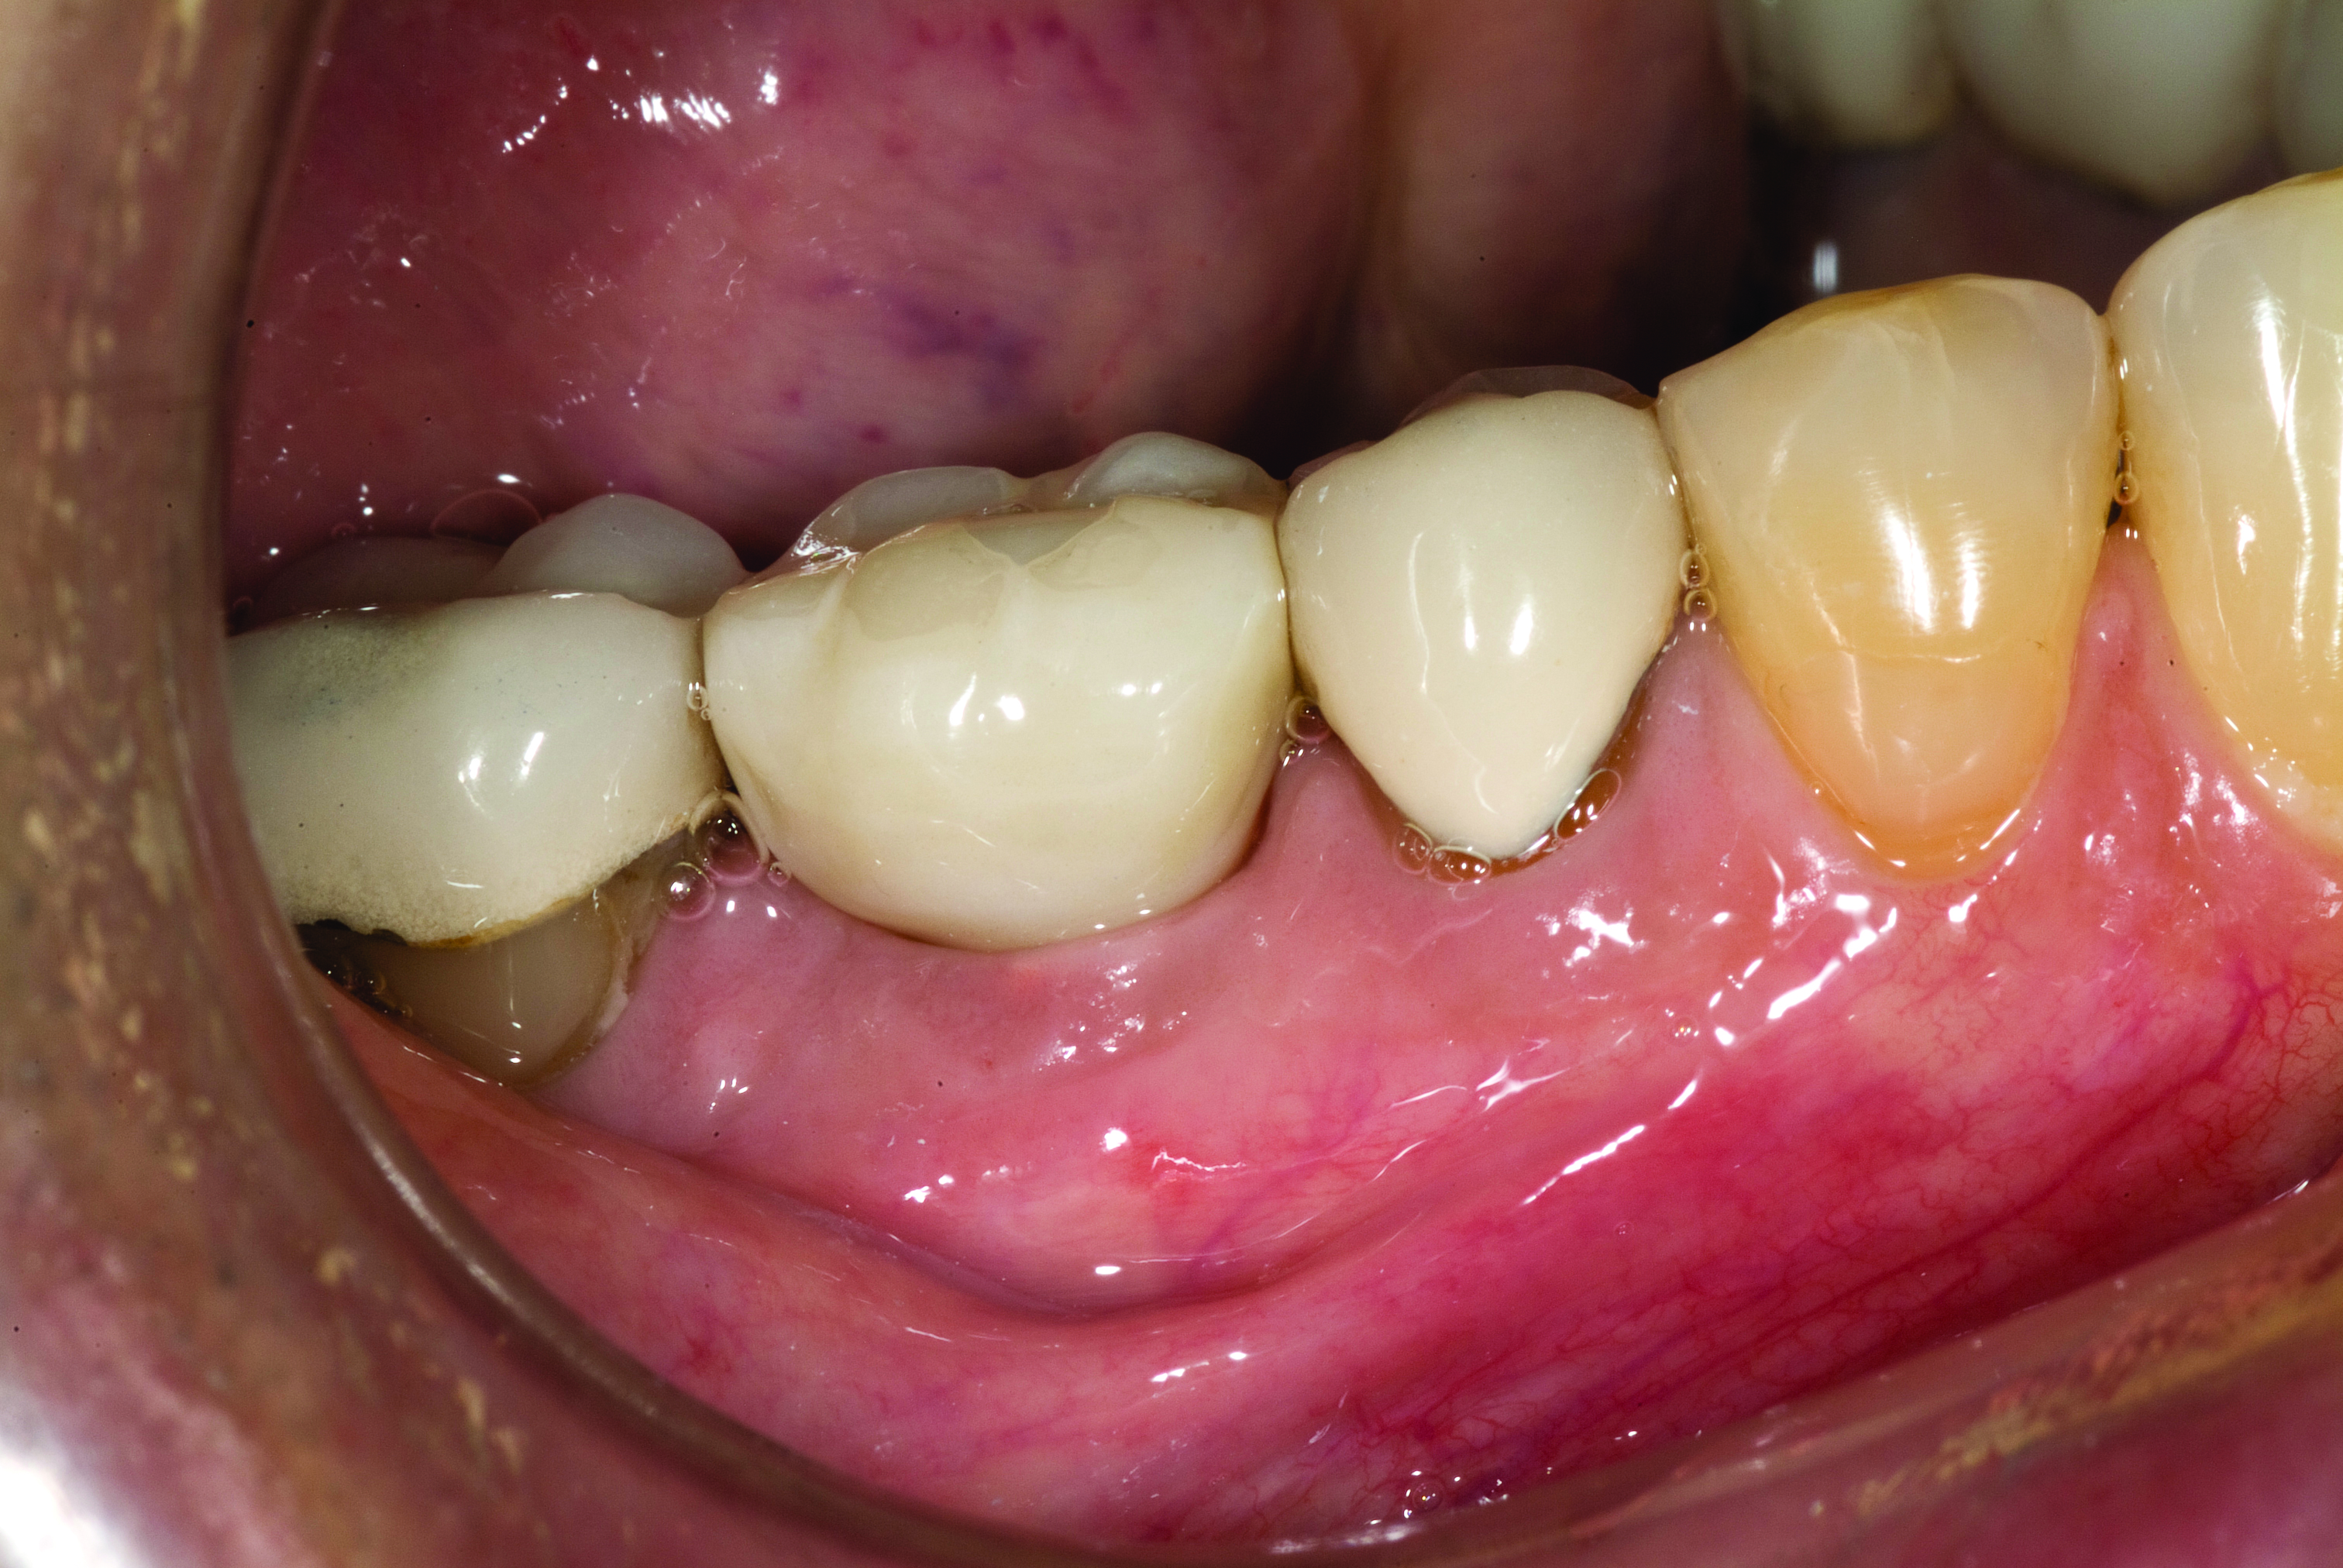

A mandibular right first molar was extracted due to an advanced Class III furcation and an irreversible pulpitis—a combination lesion. An immediate implant placement protocol was elected, and a PEEK abutment was placed on the implant (Figure 1). After 3 months of healing, a scan body was placed on the osseointegrated implant (Figure 2 and Figure 3), and an intraoral scan was taken (TRIOS Pod) (Figure 4) for the fabrication of a screw-retained crown.

Once the STL file generated from the intraoral scanner was sent to the laboratory (Figure 5), the technician used proprietary software to design the crown (Figure 6 through Figure 8), mill the crown, and digitally print a SLA model (Dental SG, Formlabs, www.formlabs.com) (Figure 9 through Figure 11), and then finish the crown on the digitally printed model. The angulated screw-channel full-zirconia crown (Nobel Biocare) (Figure 12) was seated, and contacts were evaluated intraorally and adjusted extraorally. The screw-retained crown was torqued to 35 Ncm2, and the screw access was sealed (Figure 13 through Figure 15).

Fig 14. Screw-retained implant crown replacing missing first molar, buccal view.

Figure 14

Fig 15. Final restoration of mandibular right first molar.

Figure 15